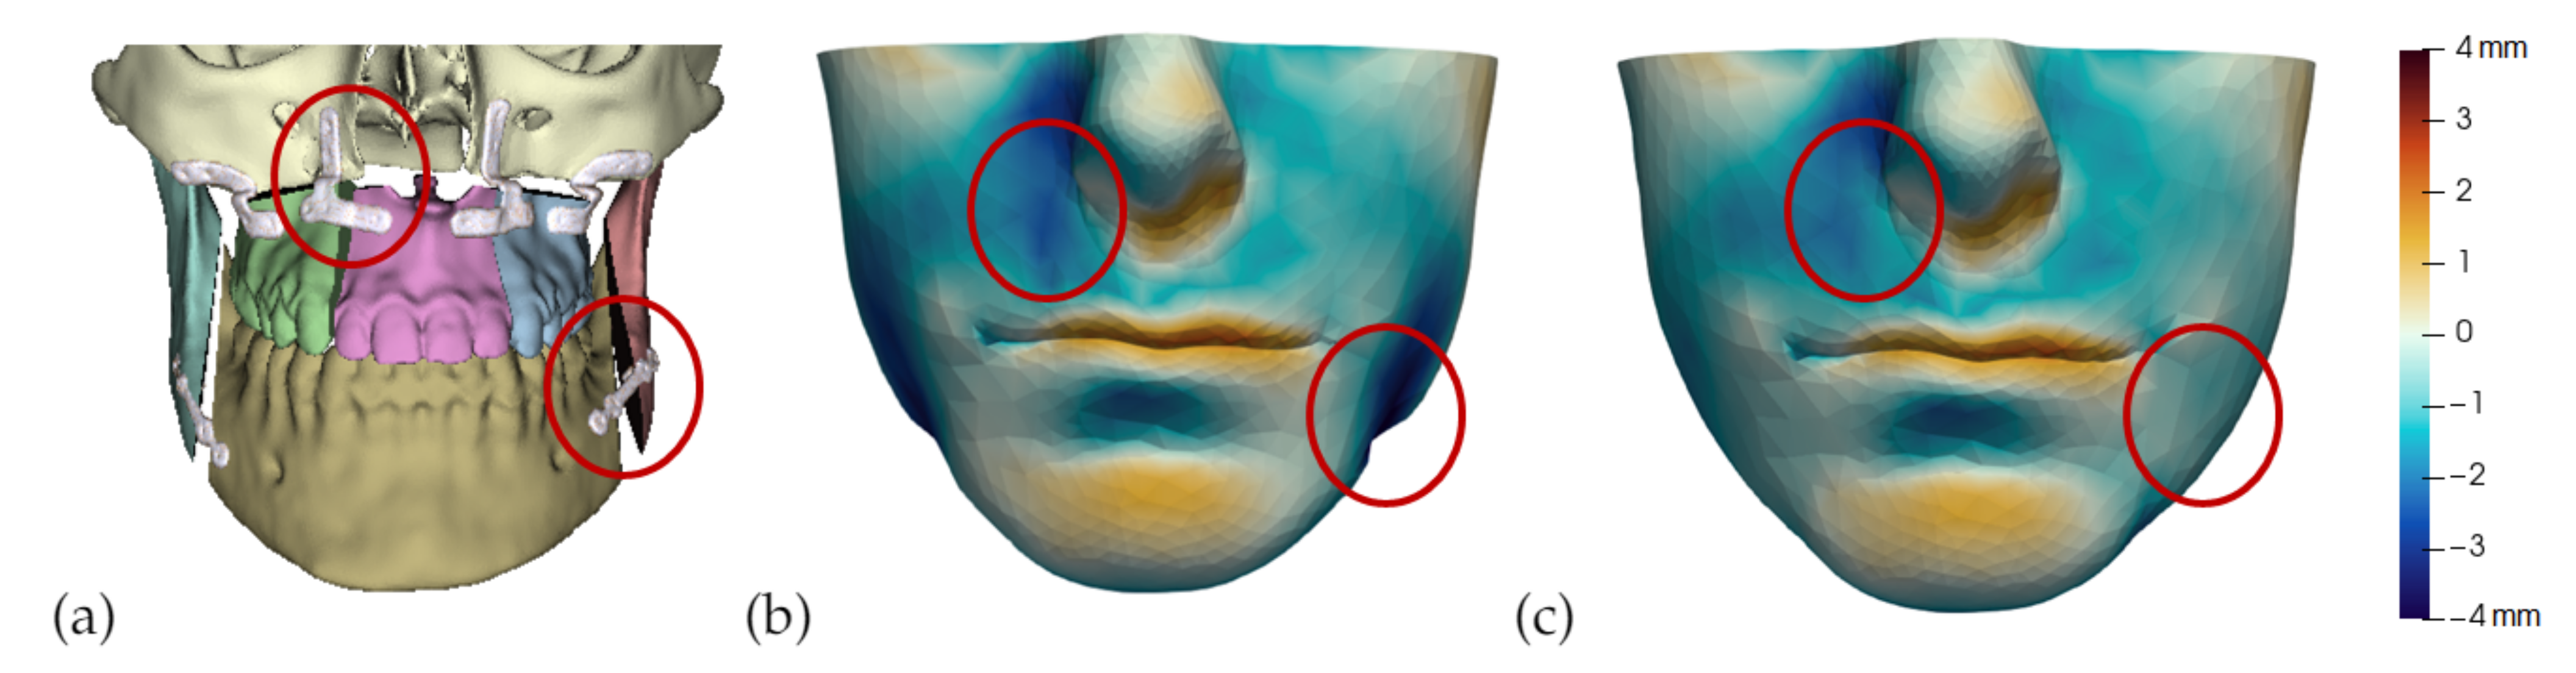

2.3.3. Smooth Coupling at Bone Cuts

- Segmentation of the maxilla and mandible. For all patients, the highest error (except for the neck, which is not clinically relevant as discussed above) appears near the cut areas, both of the maxilla (e.g., patients M5 and M7) and the mandible (e.g., patients M1 and M3). This is probably due to the presence of fixation plates and/or bone grafts in the real result (e.g., patient M10, whose maxilla was not segmented, but where the presence of bone graft has been confirmed by the surgeon who carried out the intervention). As a consequence, patients with a segmented maxilla and/or mandible show in general larger error than those without segmented bones. However, the smooth coupling method proposed in Section 2.3.3 reduces considerably the error in cut areas, as shown in Figure 2.